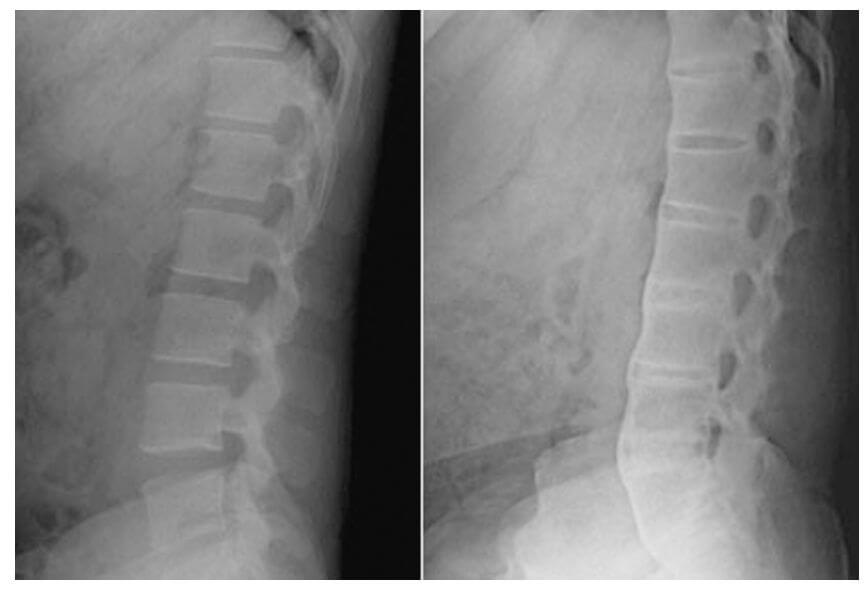

4. 강직성 척추염 진단

증상에 대한 문진 및 검진 그리고 방사선 검사로 강직성 척추염을 진단하게 됩니다.

또한 뼈 스캔(bone-scan), 컴퓨터 단층촬영(CT), 자기 공명 영상(MRI) 등을 촬영하거나 혈액검사를 통해 HLA-B27 항원 존재 유무로 판단할 수 있습니다.